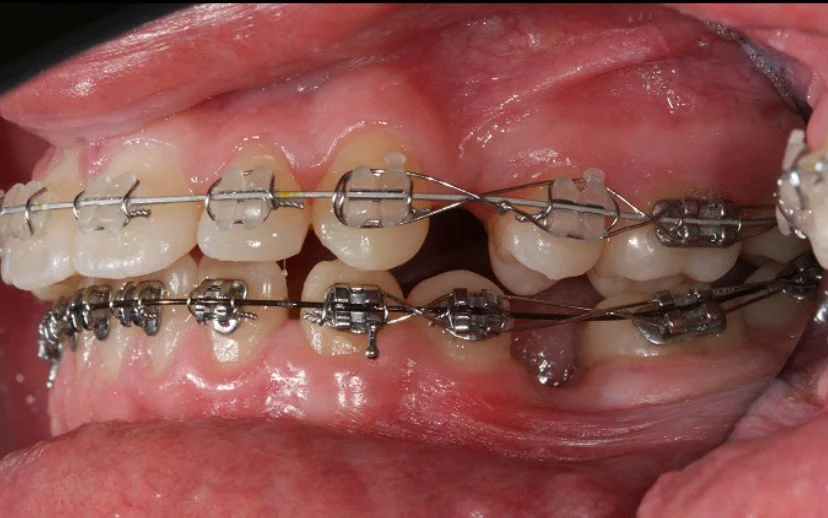

DURING

Trattamento con 4 estrazioni di una malocclusione di classe II con proclinazione degli incisivi superiori e inferiori.